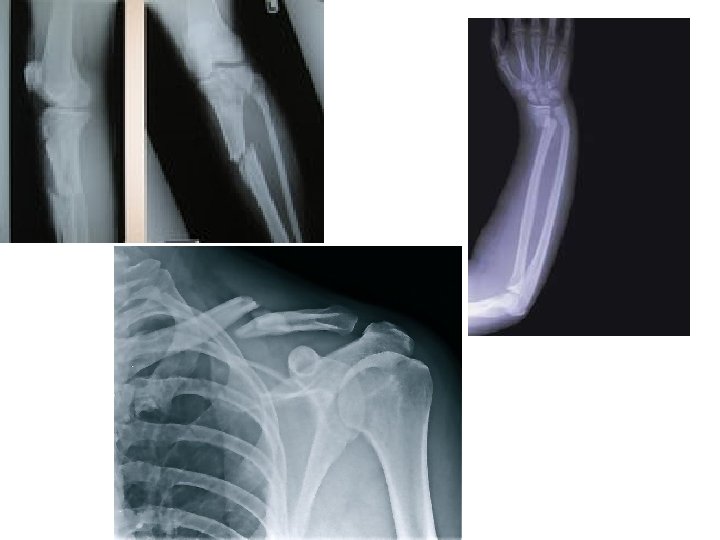

How Do Bones Repair After a Fracture? Fracture: A break in a bone.

Fractures

Bone Repair a) Blood escapes and forms a hematoma. b) Chrondrocytes fill gap with fibrocartilage. Soft callus is formed. c) Spongy bone is deposited by osteoblasts. (Bony callus formed. ) d) Bone remodeling occurs: Osteoclasts will remove excess bone of callus and reconstruct shaft walls until remodeled area looks resembles original unbroken region.